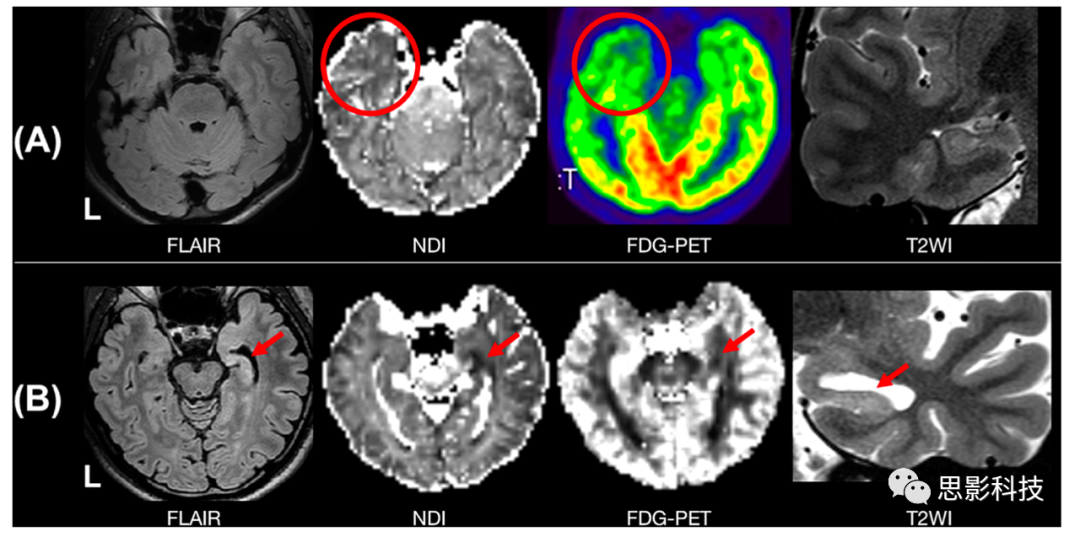

TLE)作為成人中最常見的癲癇,發(fā)現(xiàn)顳葉NDI減低,并在致癇灶同側(cè)半球異常更明顯。值得注意的是,TLE患者NDI減低,但結(jié)構(gòu)MRI未發(fā)現(xiàn)異常,其減低程度低于MRI陽(yáng)性的TLE患者(圖5)。在一項(xiàng)連接組學(xué)研究中,采用以NODDI參數(shù)作為大腦網(wǎng)絡(luò)結(jié)構(gòu)連接束的權(quán)重,發(fā)現(xiàn)在左側(cè)和右側(cè)TLE之間存在不同的網(wǎng)絡(luò)改變模式。纖維束追蹤與網(wǎng)絡(luò)分析均有其局限性,結(jié)合NODDI的局限性,在解釋數(shù)據(jù)時(shí)應(yīng)加倍謹(jǐn)慎。盡管如此,研究采用multi-shell MRI在局灶性癲灶外腦損傷及其與術(shù)后癲癇控制的關(guān)系的研究值得鼓勵(lì)。

5. 顳葉癲癇的NODDI研究

A.1MRI陰性的左顳葉癲癇患者。在致癇灶(圓圈)同側(cè)的顳尖觀察到神經(jīng)突密度指數(shù)(NDI)下降。

B. MRI陽(yáng)性右側(cè)顳葉癲癇(海馬硬化)患者。海馬區(qū)NDIODI降低(箭頭)。